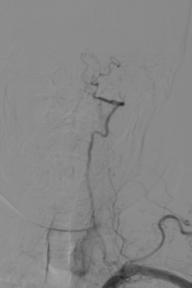

辅助检查(DSA)

R-CA

波科支架怎么样径技-弓上病例大赏|第210期·右侧颈内动脉球囊扩张术+支架植入术_https://www.jmylbn.com_新闻资讯_第12张

术后情况

术前、术后对比